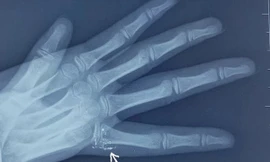

TPO - Tai nạn hi hữu do nhiễm độc thủy ngân từ nhiệt kế vỡ khiến một bệnh nhân ở Hải Phòng suýt phải cắt bỏ một phần tay đã gióng lên hồi chuông cảnh báo về cách sử dụng những thiết bị y tế tại nhà. Theo bác sĩ, lượng thủy ngân trong nhiệt kế rất ít nhưng có thể dẫn đến các vấn đề về thận, phổi, não và hệ thần kinh nếu không được xử lý đúng cách.